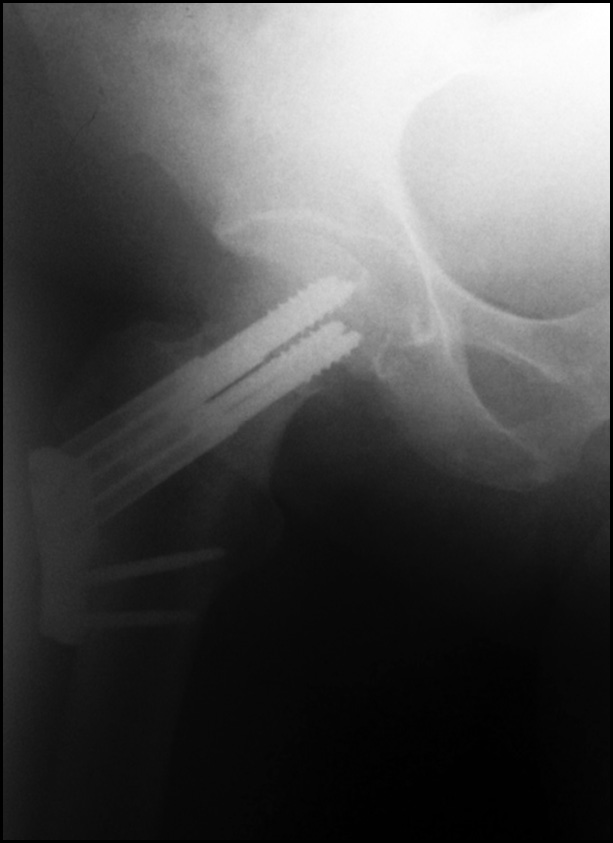

В 8 наблюдениях группы исследования (7%) при остеосинтезе с помощью ДДФ была допущена техническая ошибка при расположении пластины относительно диафиза БК, что привело к отстоянию пластины от кости (рис. 4). Послеоперационный ортопедический режим у таких пациентов не отличался от такового других больных группы исследования. При этапных контрольных осмотрах пациентов с использованием рентгенологических исследований осложнений не выявлено. Таким образом, установлено, что эта техническая ошибка не влияет на сращение перелома ШБК, не приводит к миграции фиксаторов и не увеличивает риск патологических периимплантных переломов в отдалённом послеоперационном периоде.

Рис. 4. Рентгенограмма пациента с отстоянием пластины от диафиза бедренной кости.

Fig. 4. X-ray of a patient with a plate distance from the femoral shaft.